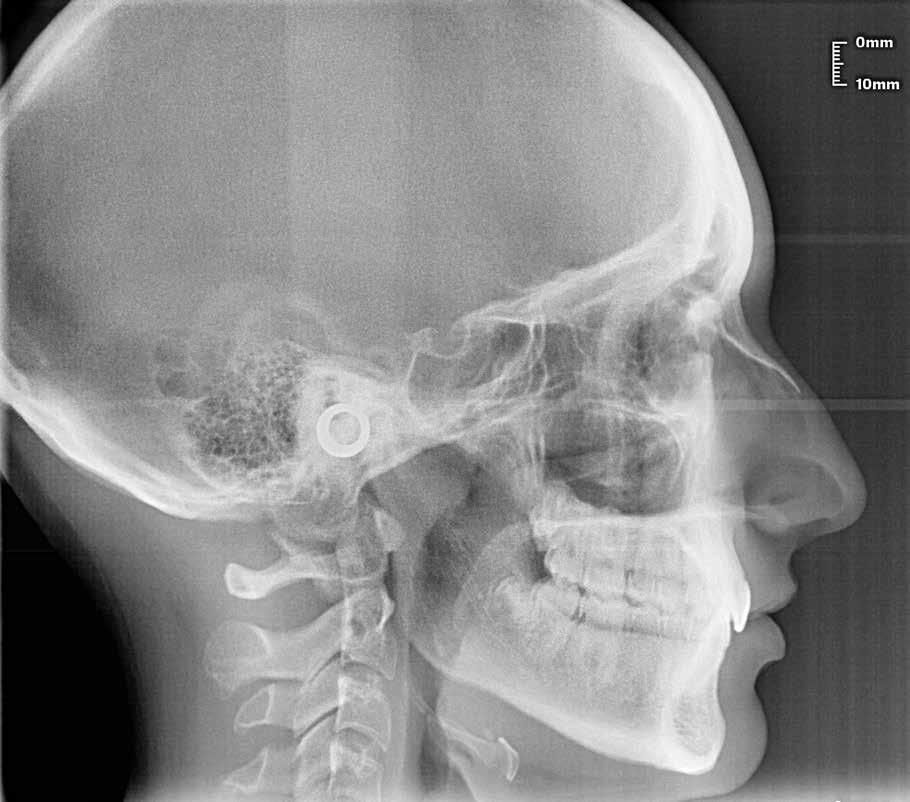

Alla risoluzione della malocclusione scheletrica e dentale si associa un netto recupero della postura con conseguente miglioramento della curva cervicale, come è possibile verificare nella teleradiografia finale.

47 46 ESTETICA FUNZIONE POSTURA Valori cefalometrici a 10 anni : ANB ANB 2.70 Posizione del Mascellare SNA 78,70 Posizione della Mandibola SNB 76.0 Angolo Articolare SArGo 142,76 Angolo Goniaco ArGoMe 125,73 Angolo incisivo inf^Corpo madibolare IiMand 92,00 Angolo incisivo Sup^Base Cranica Ant. IsCran 96,00 Angolo Interincisivo II 130,0 53 _ Esame Cefalometrico a dieci anni. 54 _ Tabella dei valori cefalometrici a dieci anni. 55 _ Ortopantomografia di controllo a dieci anni. 56 _ Teleradiografia di controllo con evidente stabilità del caso dal punto di vista scheletrico/posturale.

> La documentazione a dieci anni mostra la stabilità del caso e

come l’occlusione, elastodonticamente individuata, costituisca anche la contenzione stessa. La paziente ha smesso di

Considerazioni

indossare l’apparecchio elastodontico dopo due anni e mezzo di terapia, conservando parametri occlusali e posturali in rapporto corretto tra loro.

Nel 2019 si è provveduto all’avulsione chirurgica degli elementi dentari 18, 28, 38 e 48.